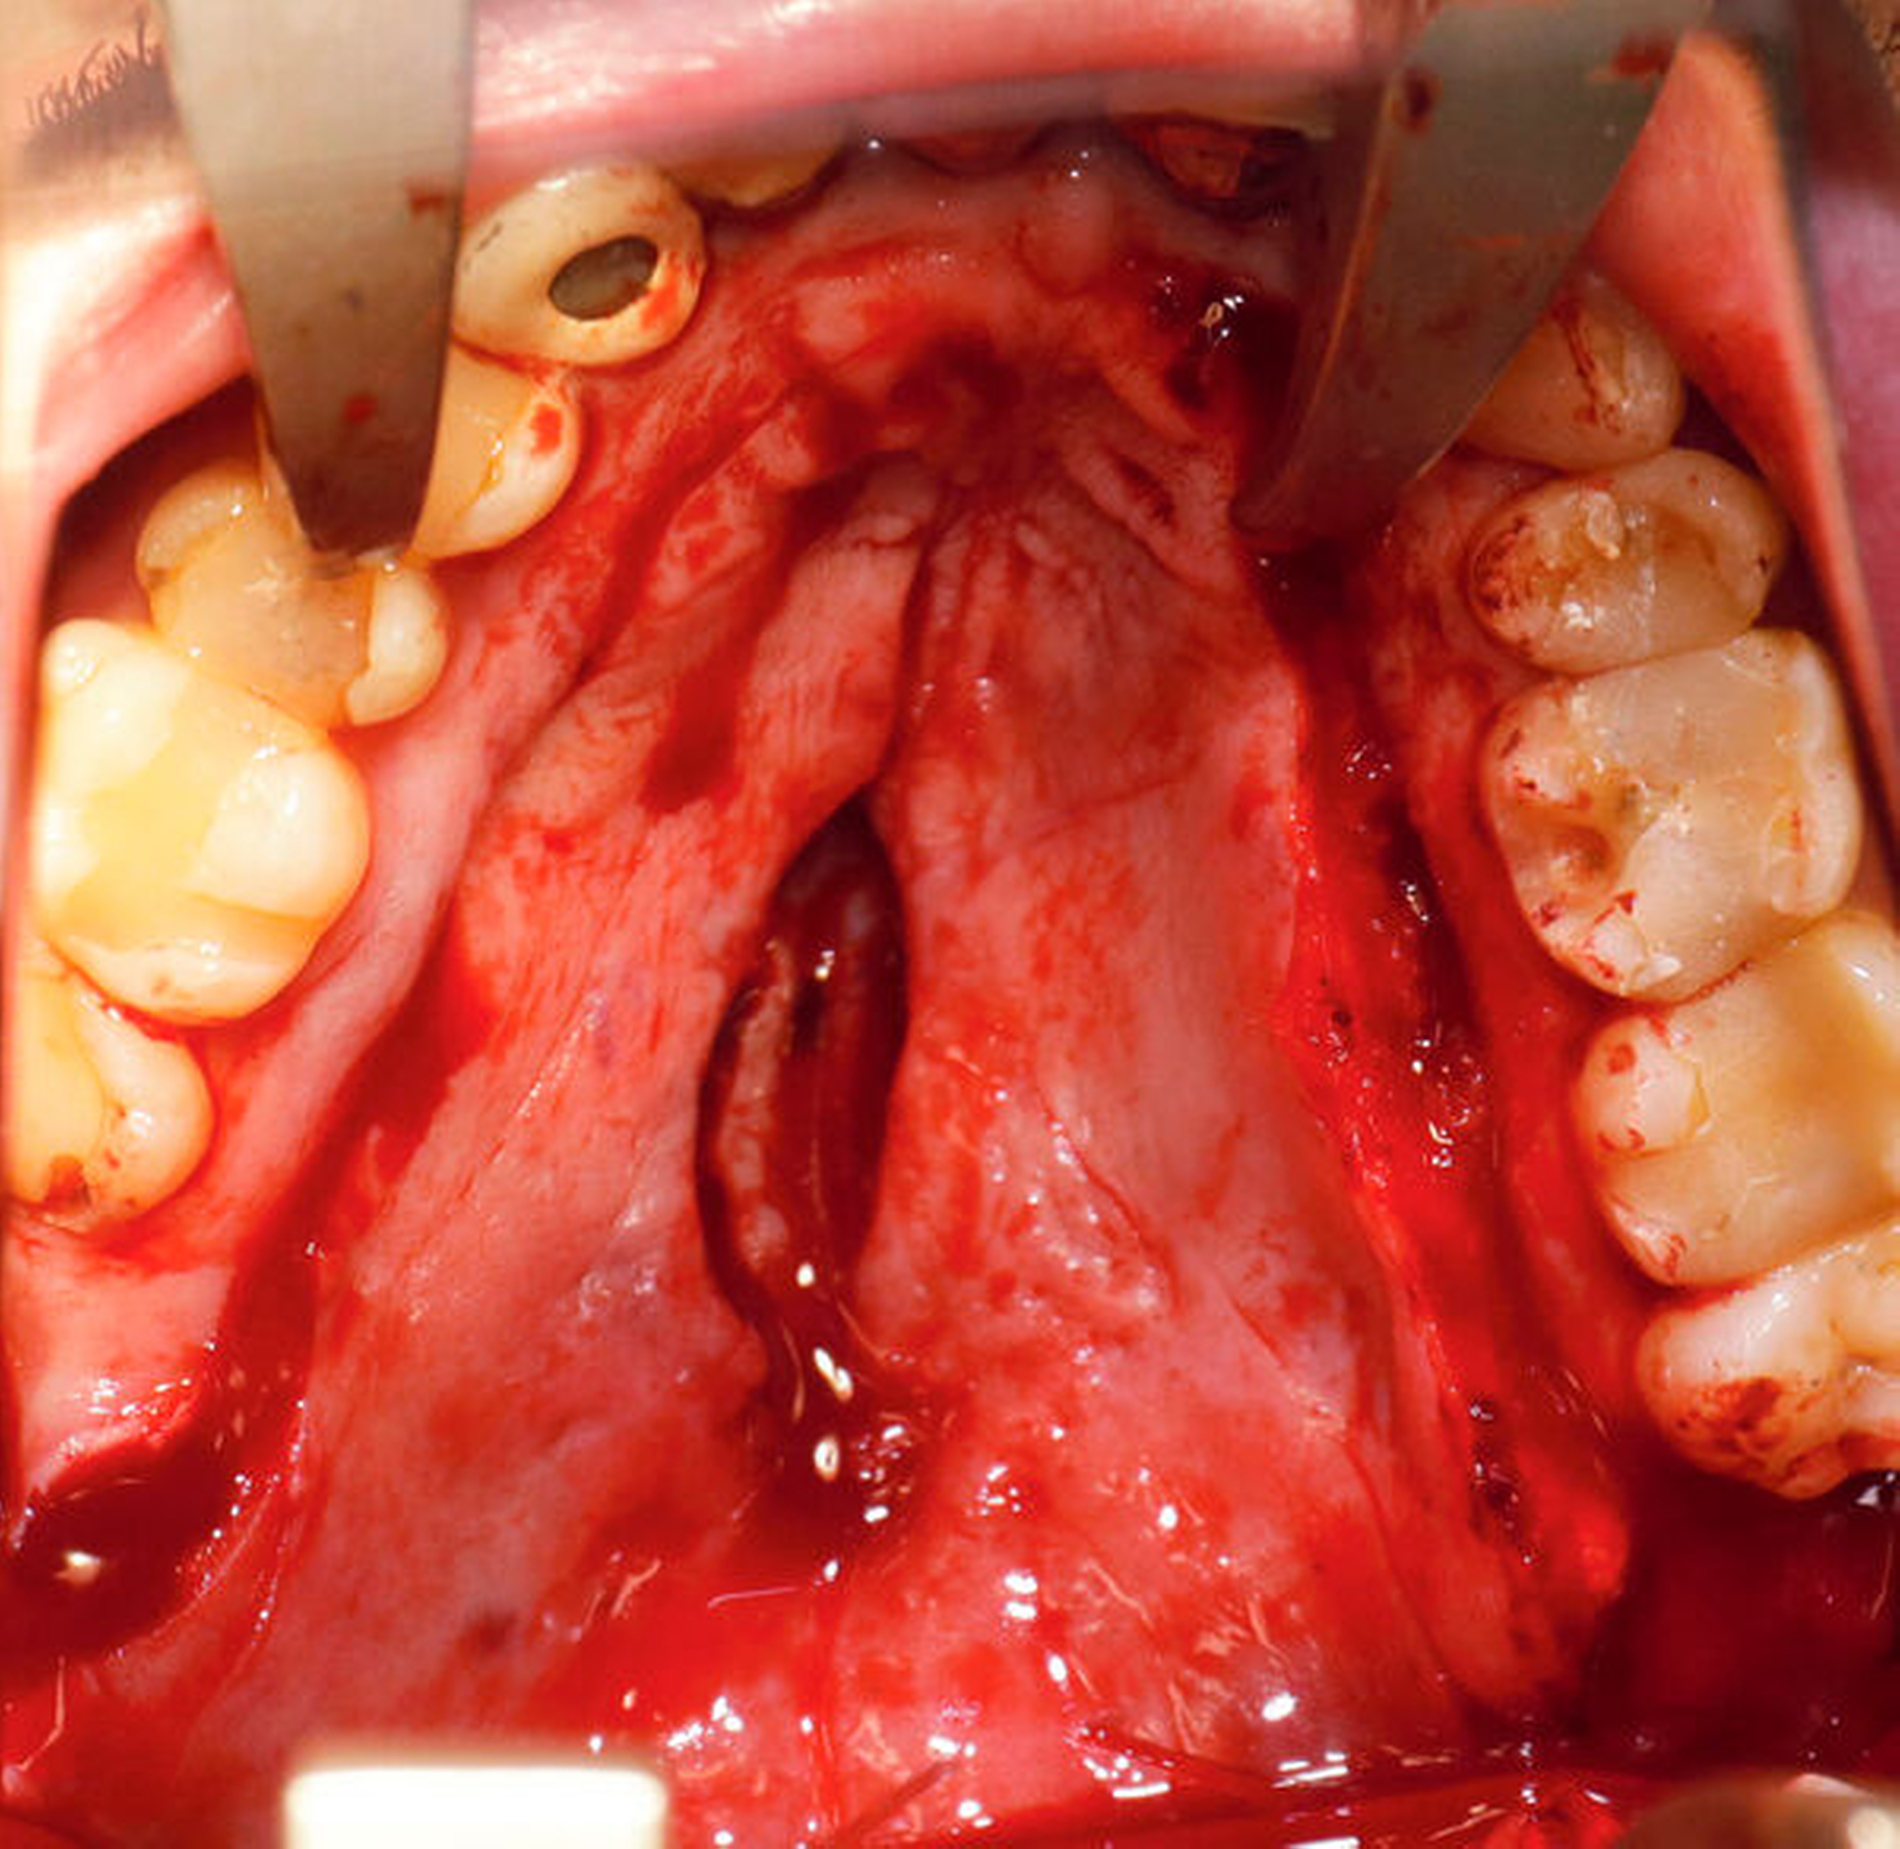

Aufgrund einer starken lokalen Entzündungsreaktion kam es intraoperativ zur mäßigen diffusen Blutung, die mit einer Salbentamponade gut gestillt werden konnte. Die Tamponade konnte am zweiten postoperativen Tag entfernt und der Patient nachblutungsfrei bis zur Besprechung des histopathologischen Befunds entlassen werden.

Nach vier Monaten konnten die internistische Therapie unter Remission bei einer deutlichen Besserung des Allgemeinzustands ausgeschlichen und der operative Defektverschluss geplant werden. Die zweischichtige Palatoplastik führten wir in oraler Intubationsnarkose unter stationären Bedingungen durch (Abbildungen 5–7).